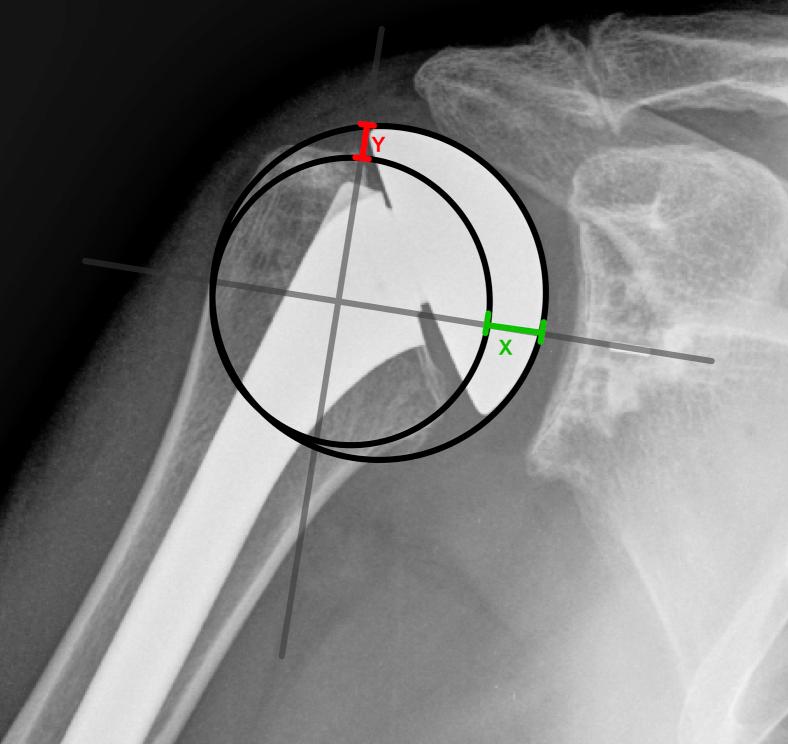

Fifty-five consecutive anatomic total shoulder arthroplasties performed using extra-short humeral heads were retrospectively reviewed and compared with age- and sex-matched controls receiving standard short heads. A total of 110 postoperative radiographs were analyzed using the Iannotti's perfect circle method to compare the prosthesis' center of rotation (COR) with the native humeral head COR. A difference in the COR of >3.0 mm was considered malpositioned. Malpositioning medially was considered overstuffed, and malpositioning laterally was considered understuffed. The direction of displacement of malpositioned prostheses was categorized using a quadrant system. Furthermore, we used a novel method to evaluate medial and superior overstuffing by measuring the displacement between the anatomic and prosthetic head positions along perpendicular axes.

回顾性分析连续55例使用超短肱骨头进行的解剖型全肩关节置换术,并与接受标准短肱骨头的年龄和性别匹配的对照组进行比较。使用伊诺蒂(Iannotti)的完美圆方法分析总共110张术后X线片,以比较假体的旋转中心(COR)与天然肱骨头的COR。COR差异>3.0mm被认为是位置不当。向内侧的位置不当被认为是过度填充,向外侧的位置不当被认为是填充不足。使用象限系统对位置不当的假体的移位方向进行分类。此外,我们使用一种新方法,通过测量解剖头和假体头位置沿垂直轴的位移来评估内侧和上方的过度填充。